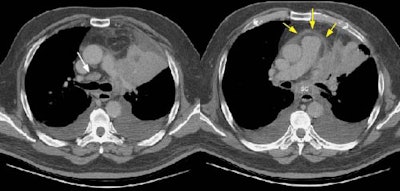

Example 2: This patient is an example of a false negative CT for hilar nodal metastases even when applying the suggested new criterion. The patient had a peripheral adenocarcinoma in the left upper lobe (black arrows). The left hilar node (yellow arrows) is not pathologic by size criteria, nor does it exhibit a convex margin with the adjacent lung parenchyma. This is a normal node by CT, however, at histopathologic analysis the node was positive for malignant cells.